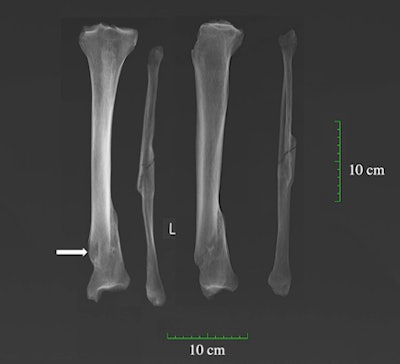

X-ray of antemortem spiral fracture of the tibia and fibula complicated by osteomyelitis (arrow indicates the cloaca) on an adult male (PSN 93) from the Hospital of St John, Cambridge.The hospital was dissolved to create St John's College in 1511 and was excavated by the Cambridge Archaeological Unit (CAU), part of the university, in 2010 during a renovation of the College's Divinity School building. CAU excavated the Augustinian Friary in 2016 as part of building works on the university's New Museums Site. According to records, the friary acquired rights to bury members of the Augustinian order in 1290, and nonmembers in 1302 - allowing rich benefactors to take a plot in the friary grounds.